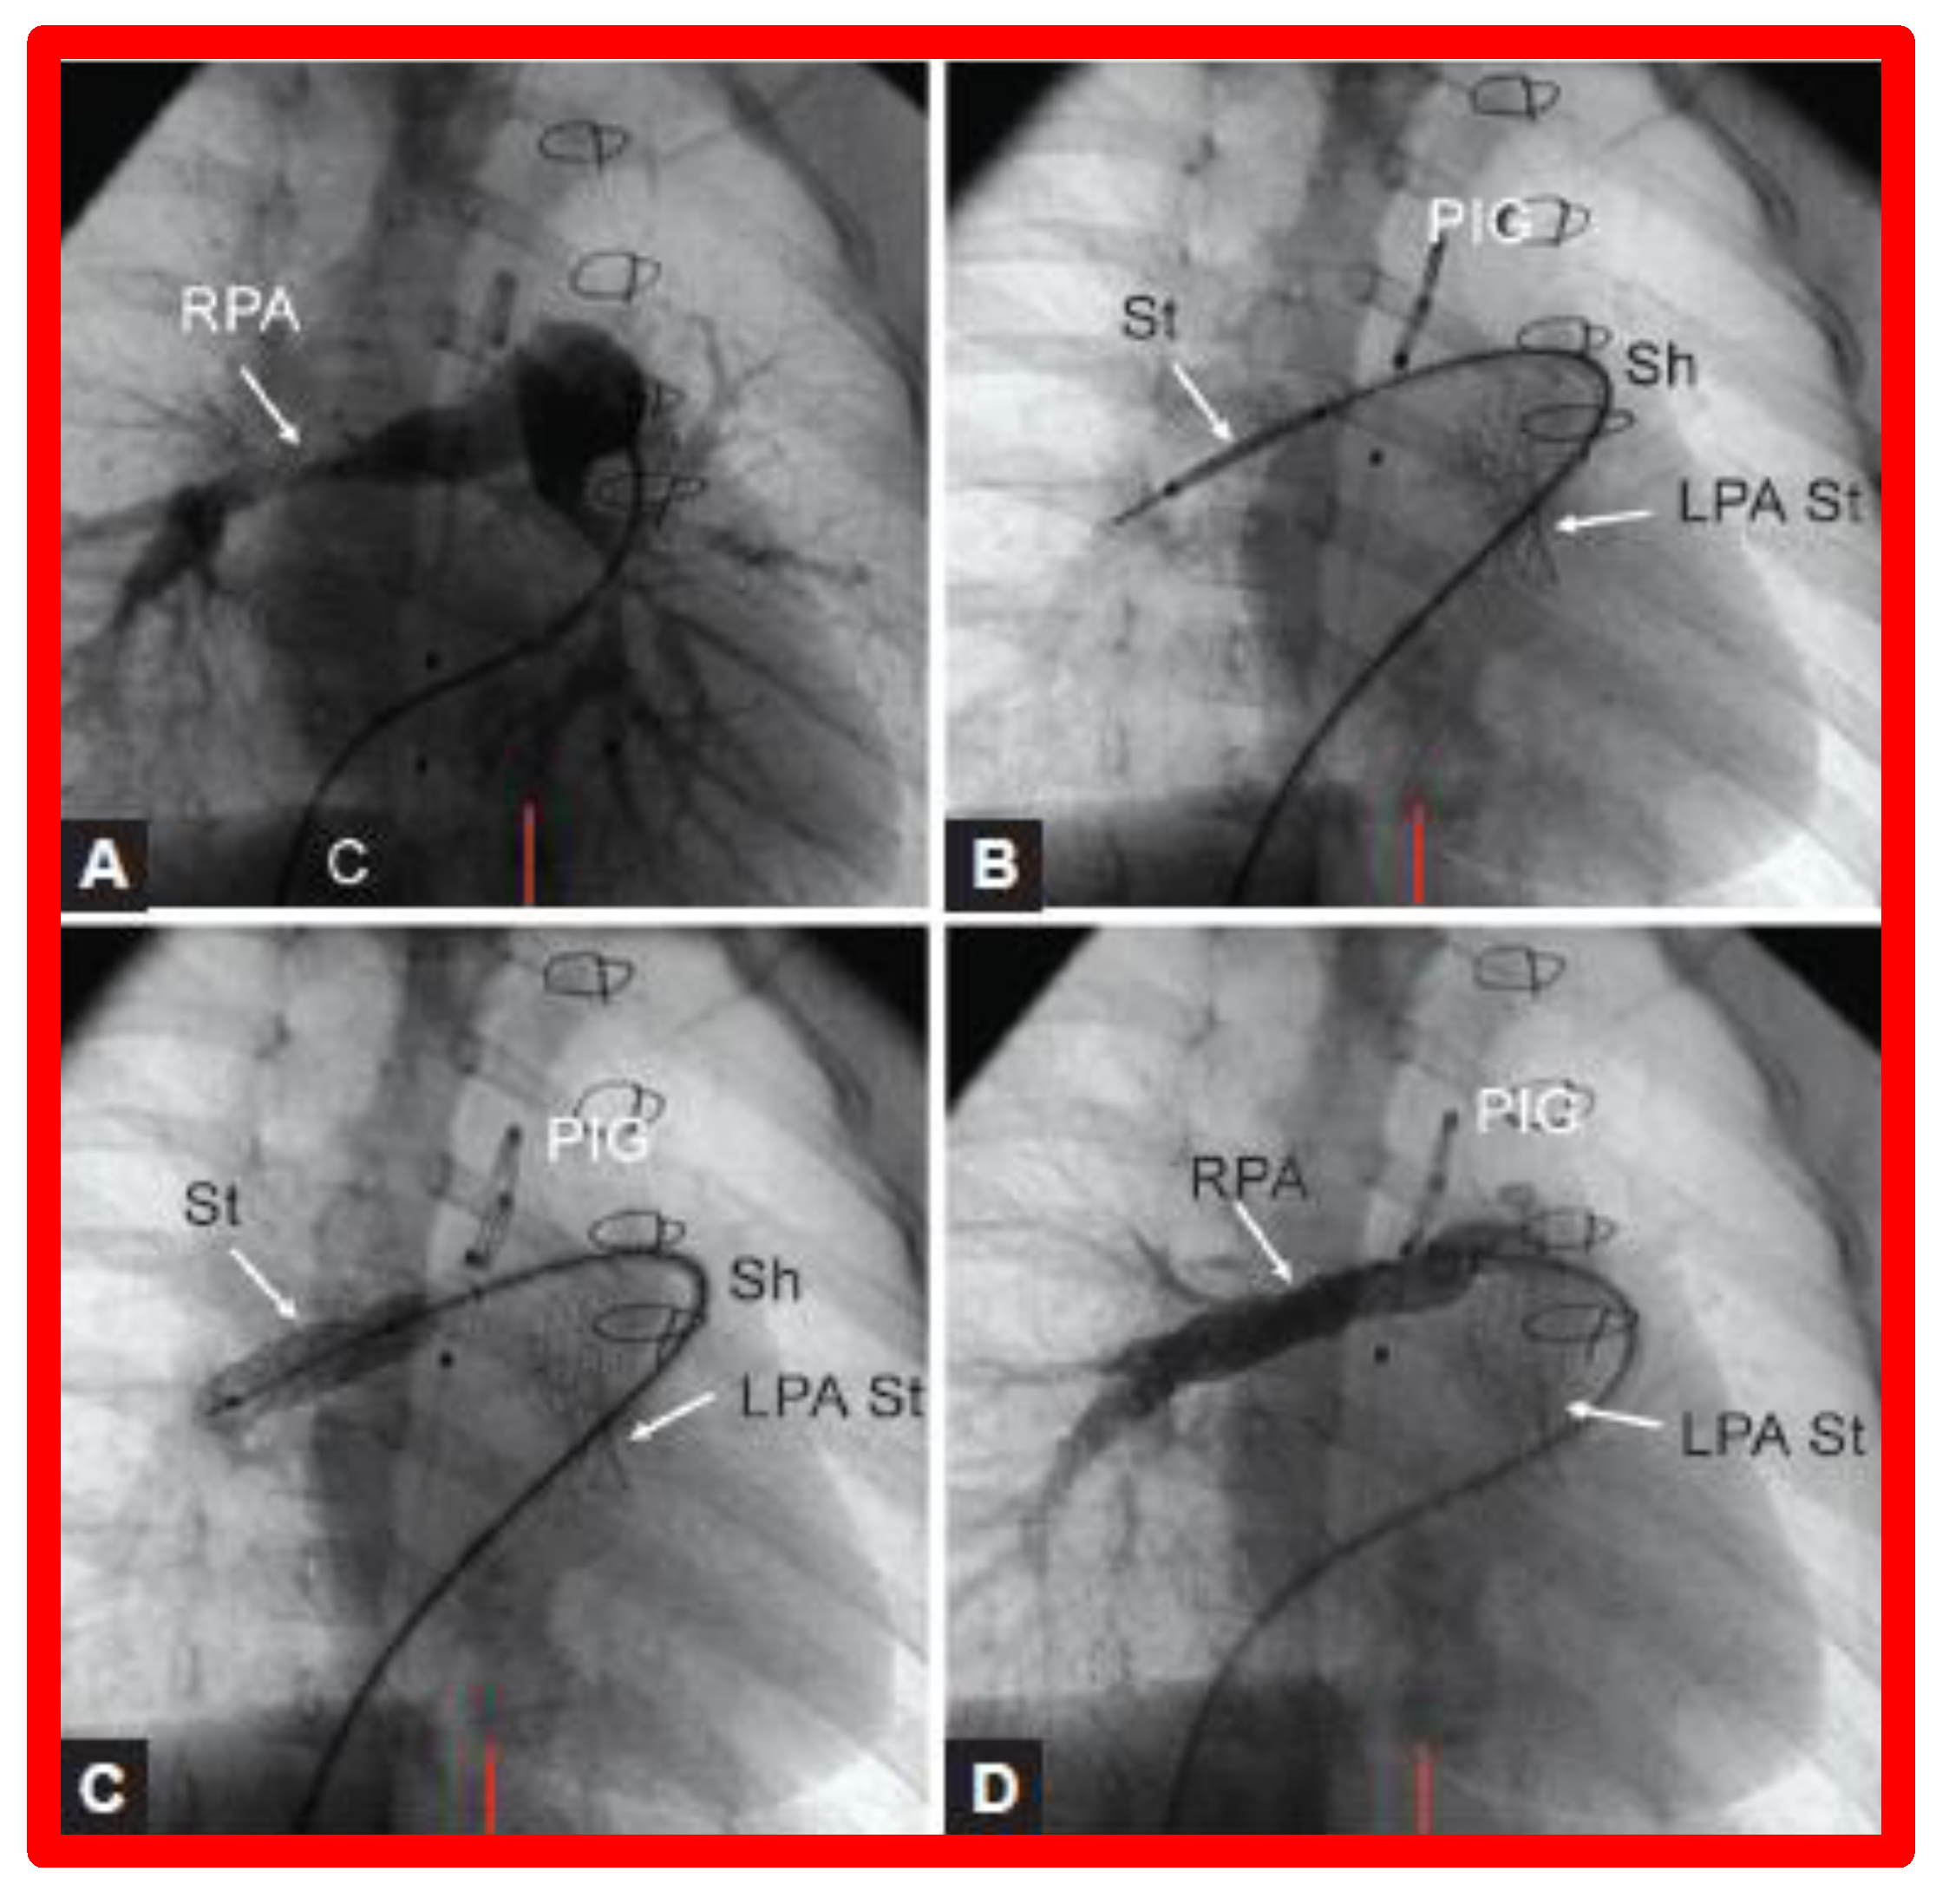

- Gibbs, J.L.; Orhan, U.; Blackburn, M.E.C.; Wren, C.; Hamilton, J.R.; Watterson, K.G. Fate of stented arterial duct. Circulation 1999, 99, 2621–2625. [Google Scholar] [CrossRef]

- Alwi, M.; Choo, K.K.; Latiff, H.A.; Kandavello, G.; Hasri Samion, H.; Mulyadi, M.D. Initial results and medium-term follow-up of stent implantation of patent ductus arteriosus in duct-dependent pulmonary circulation. J. Amer. Coll. Cardiol. 2004, 44, 438–445. [Google Scholar] [CrossRef]